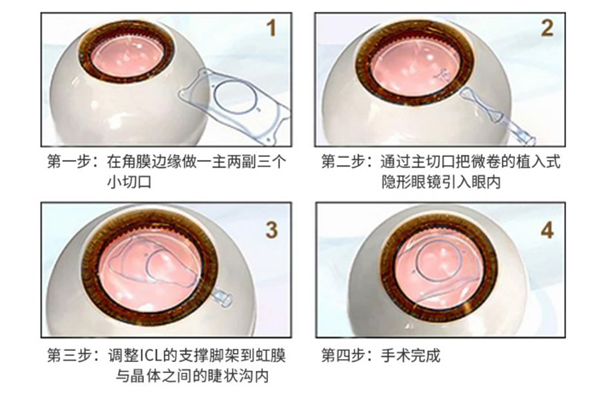

这是一种将特别定制的ICL晶体植入到眼内,来达到矫正近视、远视、散光等屈光不正问题的手术。不同于普通隐形眼镜,ICL晶体无需每天都摘下来,也没有每天佩戴不得超过8小时的要求,可以与人的眼睛和谐共处。

激光类手术需要在角膜上进行切削来达到矫正效果,类似于减法式的矫正手术。而ICL则是一种加法式矫正手术,通过植入的晶体来矫正屈光不正。这意味着,如果患者的度数有变化或出现其他视力需求,也可以找医生取出晶体。

由于ICL的结构柔软且富有弹性,因此可轻松植入眼睛内,且能在眼中保持舒适自然。这种独特的 Collamer 材料会提供紫外线防护功能,同时不影响正常的视觉效果。